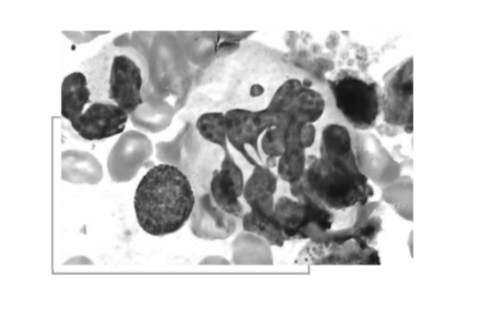

人体内专职吞噬细胞分为2类:小吞噬细胞,主要是中性粒细胞,还有嗜酸性粒细胞;②大吞噬细胞即单核吞噬细胞系统,包括末梢血液中的单核细胞和淋巴结、脾、肝、肺以及浆膜腔内的巨噬细胞、神经系统内的小胶质细胞等。

巨细胞病毒

中性粒细胞